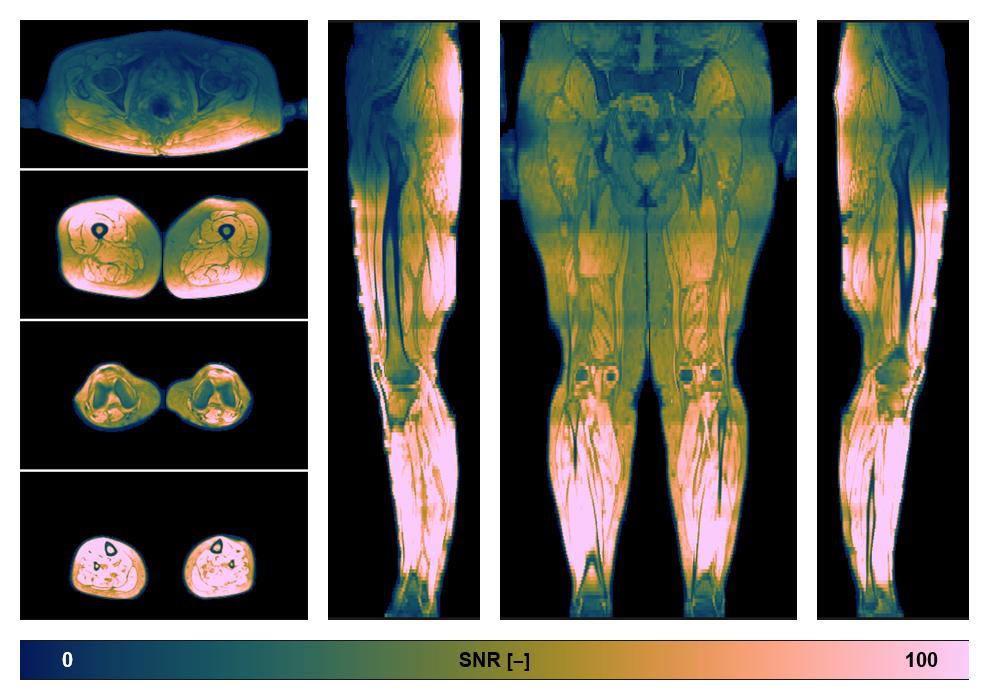

• SNR of the unweighted image

SNR distribution of the unweighted diffusion data.